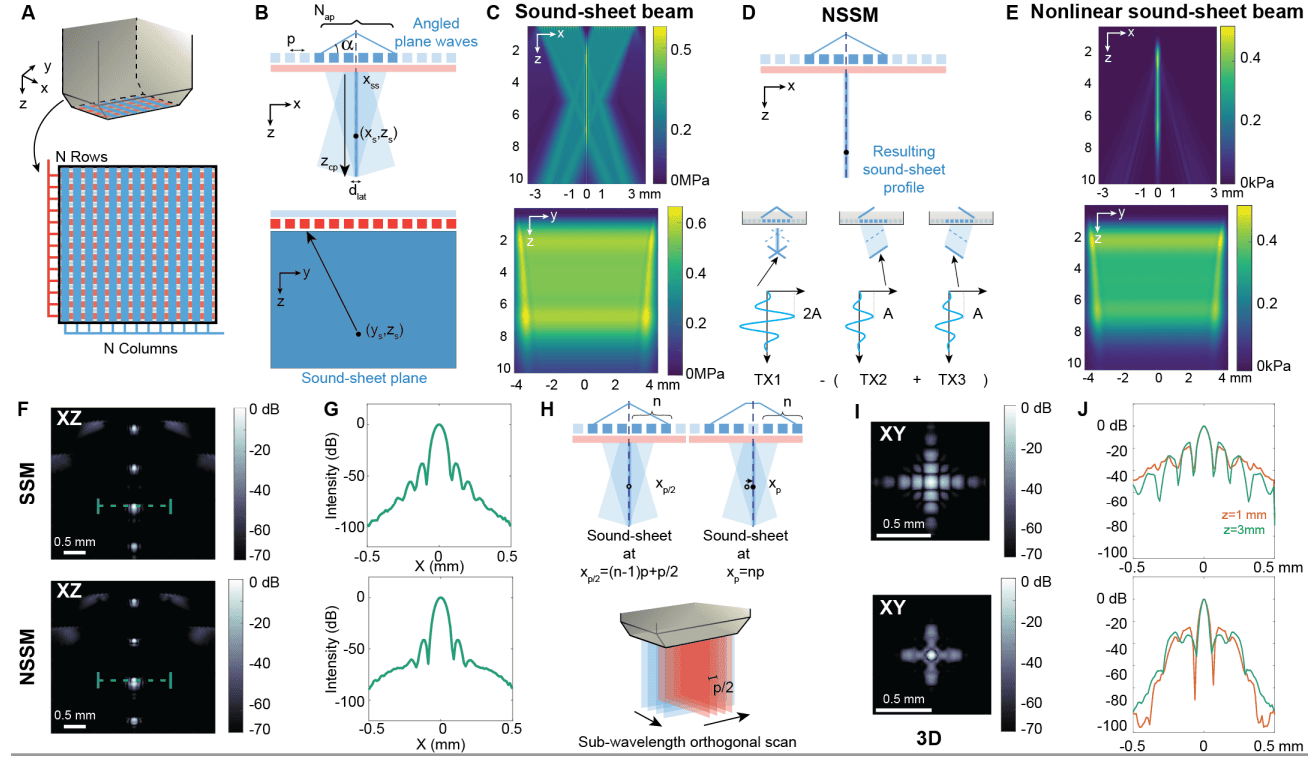

В парадигме NSSM субапертура элементов RCA-преобразователя Nap (1A) используется для передачи перекрестно распространяющихся ультразвуковых плоских волн или X-волн из двух соседних полуапертур под углами α и −α (1B). Эта пространственно структурированная ультразвуковая передача приводит к возникновению недифракционного поля акустического давления в плоскости XZ, демонстрирующего двойное акустическое давление вдоль главного лепестка луча, и плосковолнового акустического поля давления в плоскости YZ (1C).

Акустическое давление далее модулируется вдоль главного лепестка недифракционного луча с использованием последовательности импульсов перекрестной амплитудной модуляции (xAM от cross amplitude modulation) (1D), которая ограничивает нелинейное рассеяние тонким звуковым листом с постоянной шириной луча независимо от глубины (1E). Звуковой листовой луч простирается до глубины перекрестного распространения zcp = Nap / 2, которая обычно составляет порядка 100λ. 2D-изображения реконструируются из отраженных ультразвуковых эхо-сигналов, полученных на элементах ортогональной решетки RCA (1B), с использованием алгоритма формирования луча с задержкой и суммой.

Функции рассеяния точки (PSF от point spread function) резонансных MB сообщаются (1F) для линейной визуализации или SSM (т. е. только передача TX1) и NSSM (т. е. передачи TX1-TX2-TX3). Ученые выбрали MB в качестве нелинейных точечных целей при моделировании, а не GV, поскольку известны уравнения, регулирующие их вибрацию в ультразвуковом поле. Изображения SSM и NSSM в плоскости XZ показали схожие PSF, поскольку оба режима визуализации работают на одной и той же частоте (1G).

Для сканирования объема передачи звукового листа электронно перемещаются вдоль двух массивов RCA-преобразователя с использованием скользящей апертуры элементов (1H). Точность микросканирования (λ/2) достигается путем чередования передач с и без бесшумного элемента в центре субапертуры (1H), поскольку шаг (p) или межэлементное расстояние RCA приблизительно равно λ. 3D PSF представлены на 1I.

Было показано, что нелинейная визуализация снижает уровни вторичных лепестков 3D PSF на 12.8 дБ ± 4.4 дБ благодаря ограничению нелинейного рассеяния MB плоскостью звукового листа. С точки зрения разрешения, NSSM предоставил среднюю 3D функцию рассеяния точки 1λ х 0.6λ х 0.6λ по сравнению с 1λ х 0.9λ х 0.9λ для SSM (1J).